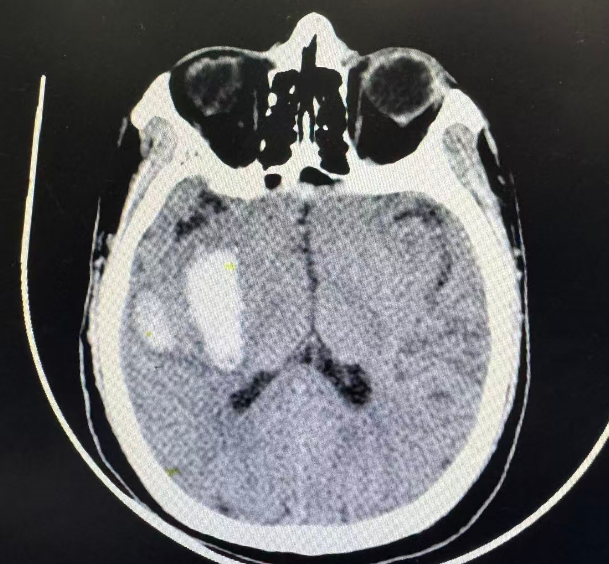

患者到院时处于嗜睡状态,精神欠佳。时间就是大脑,时间就是生命。在绿色通道保障下,颅脑CT检查被即刻优先执行。神经康复一、二科全程护航以应对检查过程中的突发状况,为后续决策抢占先机。

CT影像迅速上传至卒中中心工作群。急诊医师同步与家属沟通,清晰告知病情危重性及紧迫性:“患者急性脑出血,需要立刻入院进一步诊治。”家属的信任与配合,为抢救争取了宝贵时间。

经多学科评估后,徐大叔被收治入神经康复二科。在接下来的一周里,治疗团队密切监测大叔病情变化,实时调整治疗方案 。一周后复查颅脑CT显示:出血部分吸收,出血面积较前明显减少。这份影像报告,不仅是医疗技术的成果,更是对生命坚韧的见证。